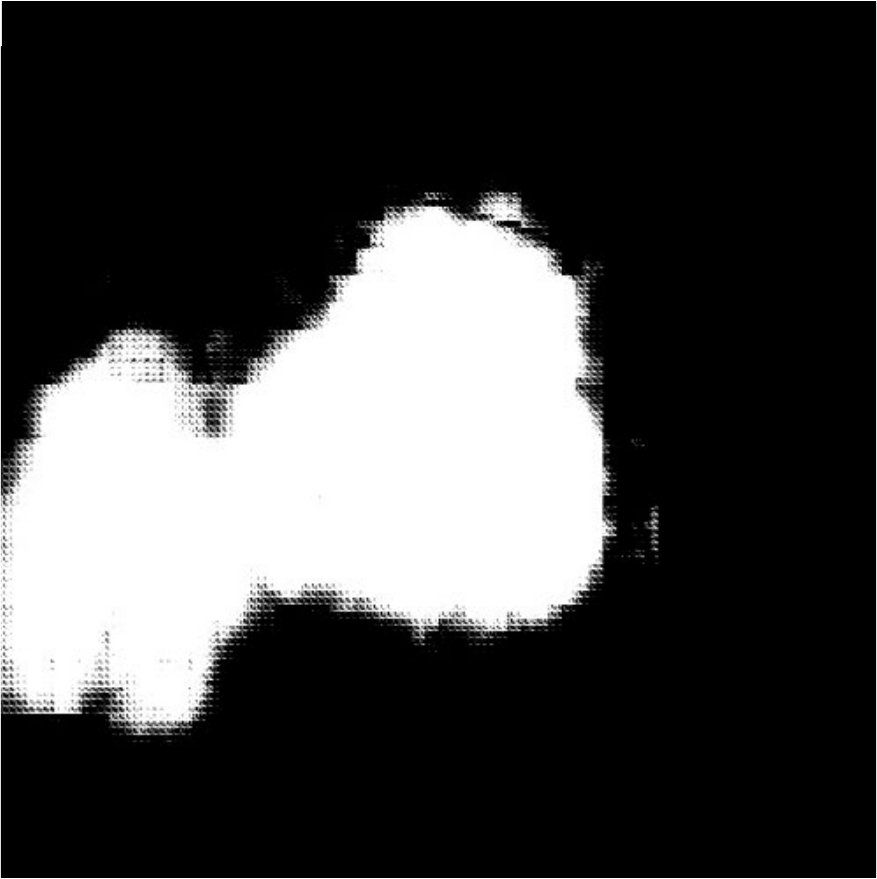

IV-C3 Results on BKAI-IGH NeoPolyp

![]() |

| (a) Inputs | (b) Ground Truth | (c) Ours | (d) EGE-UNet |

| (d) Swin-Unet | (e) MET-Net | (f) VM-UNetV2 | (g) UNet++ |

| Method | Binary | Multi-class | ||||

|---|---|---|---|---|---|---|

| MAE | Dice | IoU | MAE | Dice | IoU | |

| U-Net (2015) [1] | 0.99 | 87.25 | 81.33 | 0.92 | 67.74 | 64.11 |

| UNet++ (2020) [2] | 0.92 | 88.44 | 82.89 | 0.86 | 68.51 | 64.82 |

| EGE-UNet (2023) [28] | 3.20 | 59.98 | 49.28 | - | - | - |

| MISSFormer (2023) [8] | 0.95 | 87.98 | 81.89 | 0.87 | 70.00 | 66.40 |

| Swin-Unet (2023) [5] | 0.73 | 90.80 | 85.24 | 0.66 | 79.80 | 76.48 |

| MALUNet (2023) [29] | 1.84 | 82.09 | 69.67 | - | - | - |

| TransUNet (2024) [6] | 0.69 | 91.37 | 86.25 | 0.70 | 77.62 | 74.89 |

| MET-Net (2024) [30] | 0.74 | 91.05 | 85.99 | 0.71 | 75.96 | 73.07 |

| FSCA-Net (2024) [32] | 0.89 | 89.45 | 83.99 | 0.81 | 73.65 | 70.41 |

| VM-UNetV2 (2024) [33] | 1.26 | 87.71 | 78.16 | - | - | - |

| QTSeg (Ours) | 0.60 | 93.13 | 88.94 | 0.59 | 79.88 | 77.54 |

The experimental results of our QTSeg model on the BKAI-IGH Neopolyp dataset are presented in Table IV. The table clearly demonstrates that our QTSeg model achieves the highest scores across all metrics and tasks (binary and multi-class). Notably, QTSeg obtains the MAE, Acc, Dice, and IoU of 0.60, 99.40%, 93.13%, and 88.94%, and 0.59, 99.41%, 79.88%, and 77.54%, for the binary and multi-class tasks, respectively. Although EGE-UNet and MALUNet are characterized by their smaller parameter sizes, they struggle to converge on the poly-segmentation dataset due to inherent design limitations and model parameter constraints. In contrast, our QTSeg model demonstrates superior performance while maintaining competitive parameter values and lower FLOPs than the alternative methods. Regarding binary task, our QTSeg model achieves notable improvements of 1.76-33.15% in Dice and 2.69-39.66% in IoU. In terms of multi-class tasks, our QTSeg model gains notable improvements of 0.08-12.14% in Dice and 1.05-13.42% in IoU. The comparison in Fig. 7 showcases our model’s predictions alongside those of other methods. It is evident that our approach achieves more precise segmentation of the poly object with minimal error compared to the other methods.